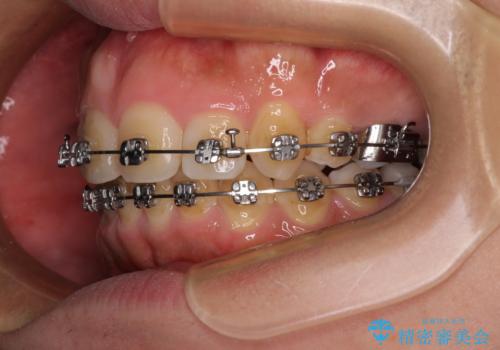

- メタルブラケット

ワイヤー矯正ということで、上顎大臼歯を後方に移動するための補助装置を併用して、積極的に前歯を引っ込めていくこととしました。

上顎歯列全体がスムーズに後方移動でき、1年で治療を終えることができました。